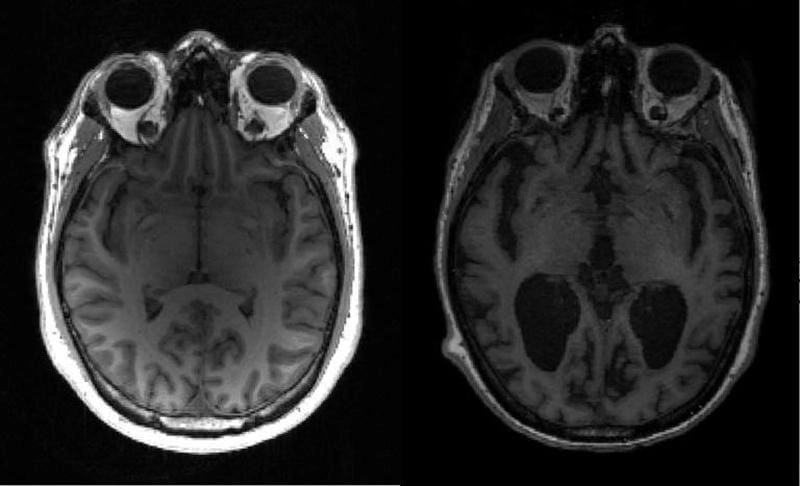

Bộ sưu tập hình ảnh bệnh alzheimer dưới kính hiển vi cho thấy sự khác biệt rõ rệt giữa não bộ khỏe mạnh và não bộ mắc bệnh. Những bức ảnh cận cảnh làm lộ rõ mảng amyloid và sợi thần kinh xoắn bất thường, nguyên nhân chính gây suy giảm trí nhớ. Mỗi bức ảnh đều kể một câu chuyện đau lòng, khắc họa hành trình từ quên lãng nhẹ đến mất hoàn toàn khả năng nhận thức của người bệnh.